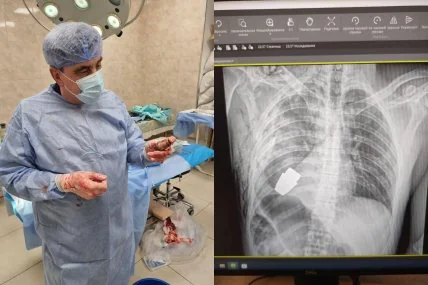

Могла вибухнути будь-якої секунди: пораненому українському захиснику витягли гранату з грудей (фото)

Український військовослужбовець отримав поранення у груди з підствольного гранатомета, але зміг вижити завдяки тому, що граната не вибухнула.

Як повідомила у своєму Telegram-каналі заступник міністра оборони Ганна Маляр, операцію із вилучення гранати проводили під наглядом двох саперів, які страхували медичний персонал.

"Операція проводилася одним із найдосвідченіших хірургів ЗСУ – Андрієм Вербою без електрокоагуляції, оскільки граната могла детонувати будь-якої миті", — написала вона.

Маляр додала, що сама операція пройшла успішно, а військовослужбовця відправили на подальшу реабілітацію та відновлення.